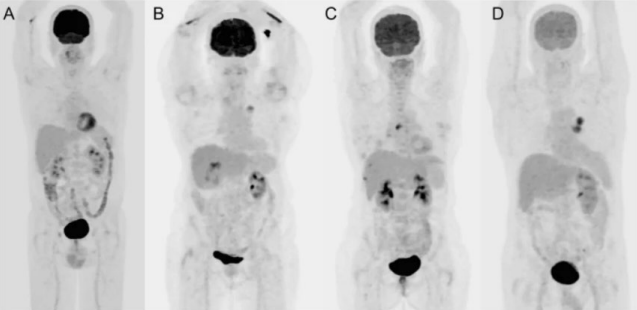

Breakdown what PET/CT is a combination of (what each part specifically scans)

PET – scans the patient’s physiology

CT – scans the patient’s anatomy

What is the skull-base to mid-thigh acquisition?

Most common acquisition for PET imaging

We would start scanning the patient from their eyes → end at their thighs

When would we perform a whole body acquisition?

If the patient has melanoma – want to image cancer from head-to-toe